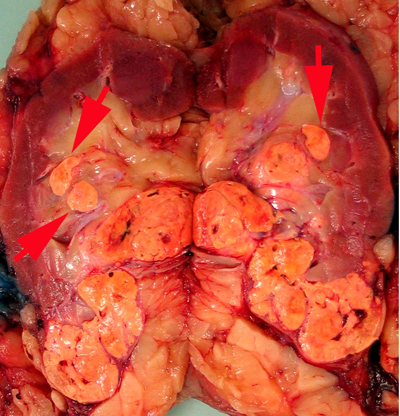

The renal sinus is the fatty tissue compartment that lies between renal parenchyma and the pelvi-calyceal system. This is a complex structure with the vascular system being anterior to the pelvi-calyceal system and the sinus extending anteriorly and posteriorly within the kidney (7). Veins entering the renal sinus have a smooth muscle media of variable thickness. Gross recognition of renal sinus involvement is often not difficult and rounded nodules in the renal sinus outside the main tumor indicate sinus vein invasion (Fig. 1A).

Figure 1A. Rounded nodules in the renal sinus indicate sinus vascular involvement.

Sinus fat invasion occurs when intravenous tumor invades through the media (33), however, in some cases tumor bulging into the sinus can be difficult to interpret. Recommendations for sampling have varied with protocols ranging from sampling of the entire interface to 2-3 blocks (6, 7, 34, 35). At the meeting there was consensus that when invasion of the renal sinus is uncertain, at least three blocks of the interface should be taken. If invasion is grossly evident or obviously not present (small peripheral tumor) only 1 block is needed to confirm the gross impression.

Sampling renal vein and vena cava

Tumor grossly involving the renal vein is usually visible to the naked eye. A tumor thrombus typically expands the renal vein (Fig. 1B) and may or may not be adherent to the renal vein wall. If the surgical margin is clamped, there is a tendency for the renal vein margin to retract back from the tumor thrombus when the clamps are removed. There was near consensus that the actual margin and additional sections of the tumor thrombus should be sampled, particularly in areas where tumor is adherent to the wall.

Figure 1B

Figure 1B. Tumor grossly involving the renal vein is usually visible to the naked eye. A tumor thrombus typically expands the renal vein. The renal vein margin (arrow) often retracts back from the tumor thrombus when vein clamps are removed.